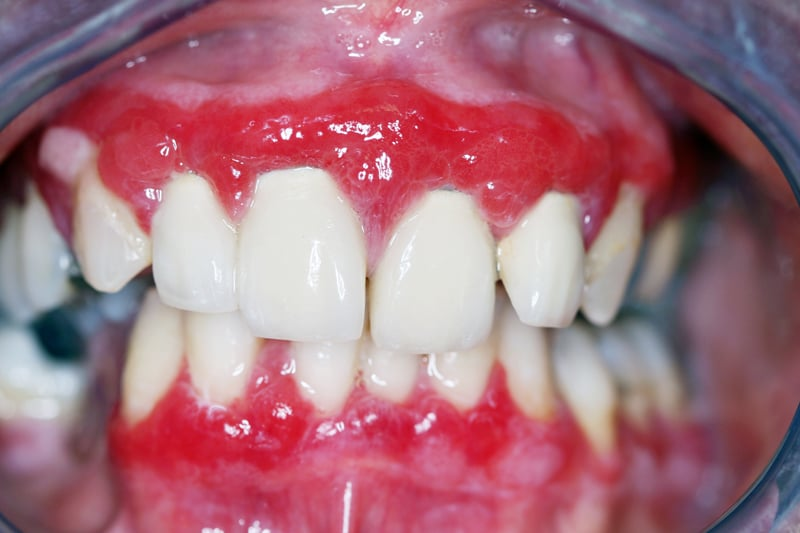

what are some examples of oral swellings? 4

Gingival Hyperplasia

Nifedipine ,Cyclosporin ,Phenytoin, Leukaemias